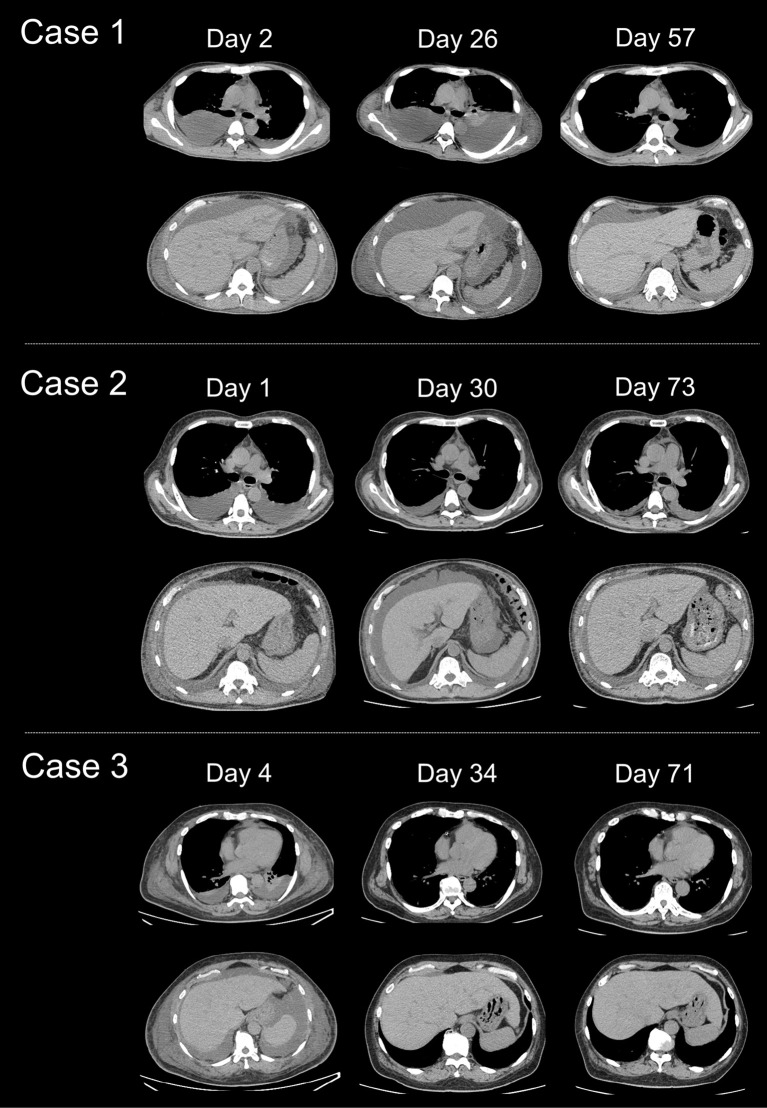

特发性多中心Castleman病(iMCD)伴血小板减少、贫血、发热、网状髓纤维化/肾功能不全和器官肿大(TAFRO),常发展为长期严重的血小板减少和多器官功能障碍,并伴有高死亡率。我们在此描述了三个iMCD-TAFRO病例,其中血清可溶性白介素-2受体(sIL-2R)水平在治疗开始后随疾病活动而变化。血小板减少在患者c反应蛋白水平正常化后持续数周至数月,而他们的sIL-2R水平在血小板恢复前10-47天正常化(≥100×109/L)。因此,血清sIL-2R测量可能是评估iMCD-TAFRO伴长期血小板减少患者疾病活动性的有效方法。

Idiopathic multicentric Castleman disease (iMCD) accompanied by thrombocytopenia, anasarca, fever, reticulin myelofibrosis/renal insufficiency, and organomegaly (TAFRO) frequently develops into prolonged severe thrombocytopenia and multiorgan dysfunction, which is associated with a high mortality rate. We herein describe three cases of iMCD-TAFRO in which serum soluble interleukin-2 receptor (sIL-2R) levels varied in relation to disease activity following the initiation of treatment. Thrombocytopenia persisted for several weeks to months after the normalization of the patients' C-reactive protein levels, whereas their sIL-2R levels normalized 10-47 days prior to platelet recovery (≥100×109/L). The serum sIL-2R measurement may therefore be an effective method for evaluating the disease activity in iMCD-TAFRO patients with prolonged thrombocytopenia.